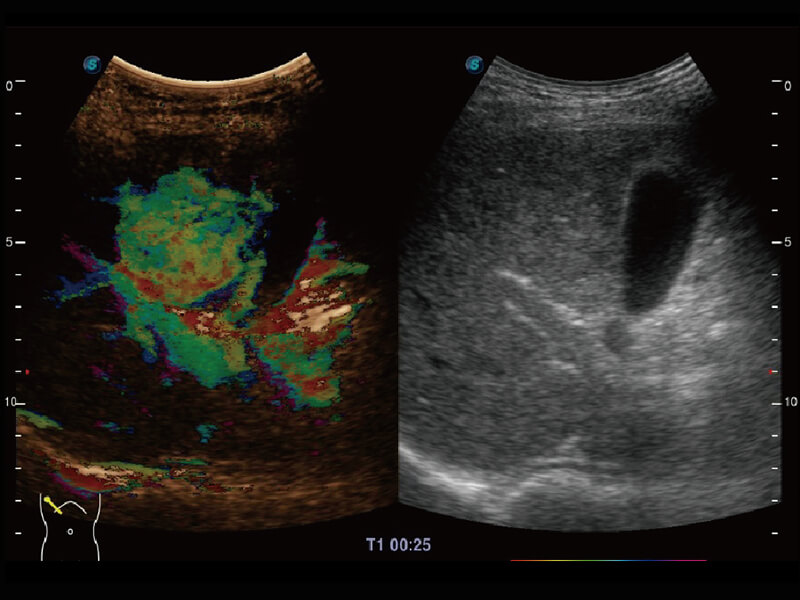

S60探头工艺,从前端信号处理每一个环节采集无损声学数据,真实还原组织原貌,再现解剖细节。